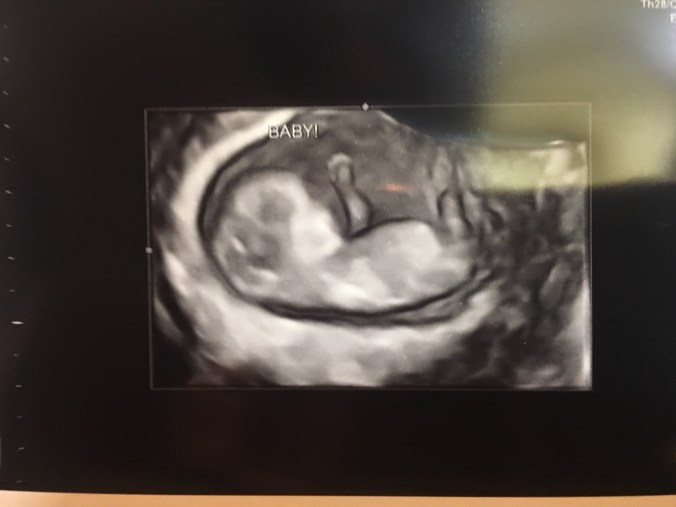

So we were incredibly shocked to discover that we are pregnant. What a scary, uncertain, and happy moment all at once, with so many emotions running together. The moment we’d feared, and wondered about, “what if we somehow, accidentally end up pregnant one day?” Obviously, there are preventions, but the fear was still there. Well, now we know what that moment feels like first hand.

We have seen a prenatal geneticist, and are planning on having an amniocentesis to find out the status of the baby’s health. This test is performed between 14 and 20 weeks and identifies genetic disease. You can read more about it here. I am currently 11 weeks and 5 days, so we will hopefully have the test around the end of this month or beginning of next month. We are still trying to get pre approval from insurance so we don’t have to pay for this costly test without any coverage.

Huff Baby #2 Due January 17, 2018